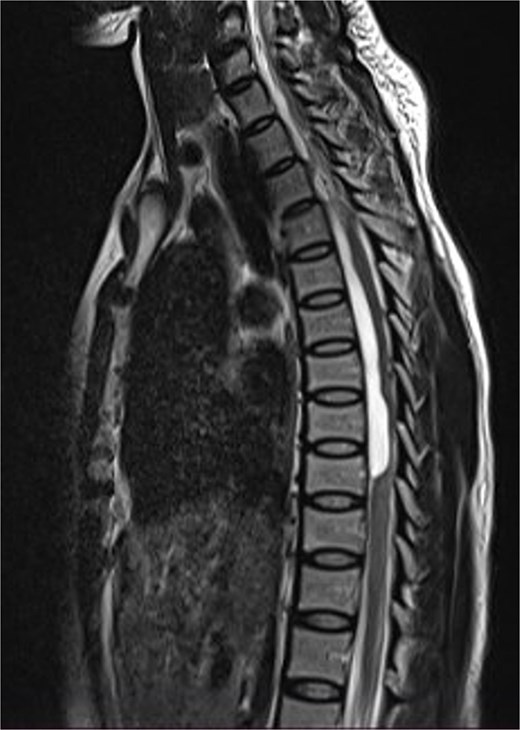

Thoracic and lumbosacral spine MRI showed an intradural-extramedullary cystic lesion, hypointense on T1 and hyperintense on T2-weighted images, extending from T5 to T9 vertebral levels with posterior displacement and flattening of the cord at the same levels (Fig. 5). There were multiple disc bulges at L3/L4, L4/L5, and L5/S1 with minimal thecal compression. A diagnosis of thoracic intradural AC was made.

Sagittal T2-weighted thoracic spine MRI images showing an anteriorly located intradural arachnoid cyst at T5–T9, posteriorly displacing and compressing the spinal cord.

The cyst was approached posteriorly through T5–T8 left hemilaminectomies. At surgery, there was a cyst anterior to and posteriorly displacing the spinal cord which was flattened. Partial cyst excision was done and water tight dura closure done. The post-operative course was uneventful, she remained neurologically the same and was discharged on the 17th post-operative day. Her first post-operative follow-up visit was 6 weeks after discharge (59 days post-surgery). At this time, she had not made any neurological gain.